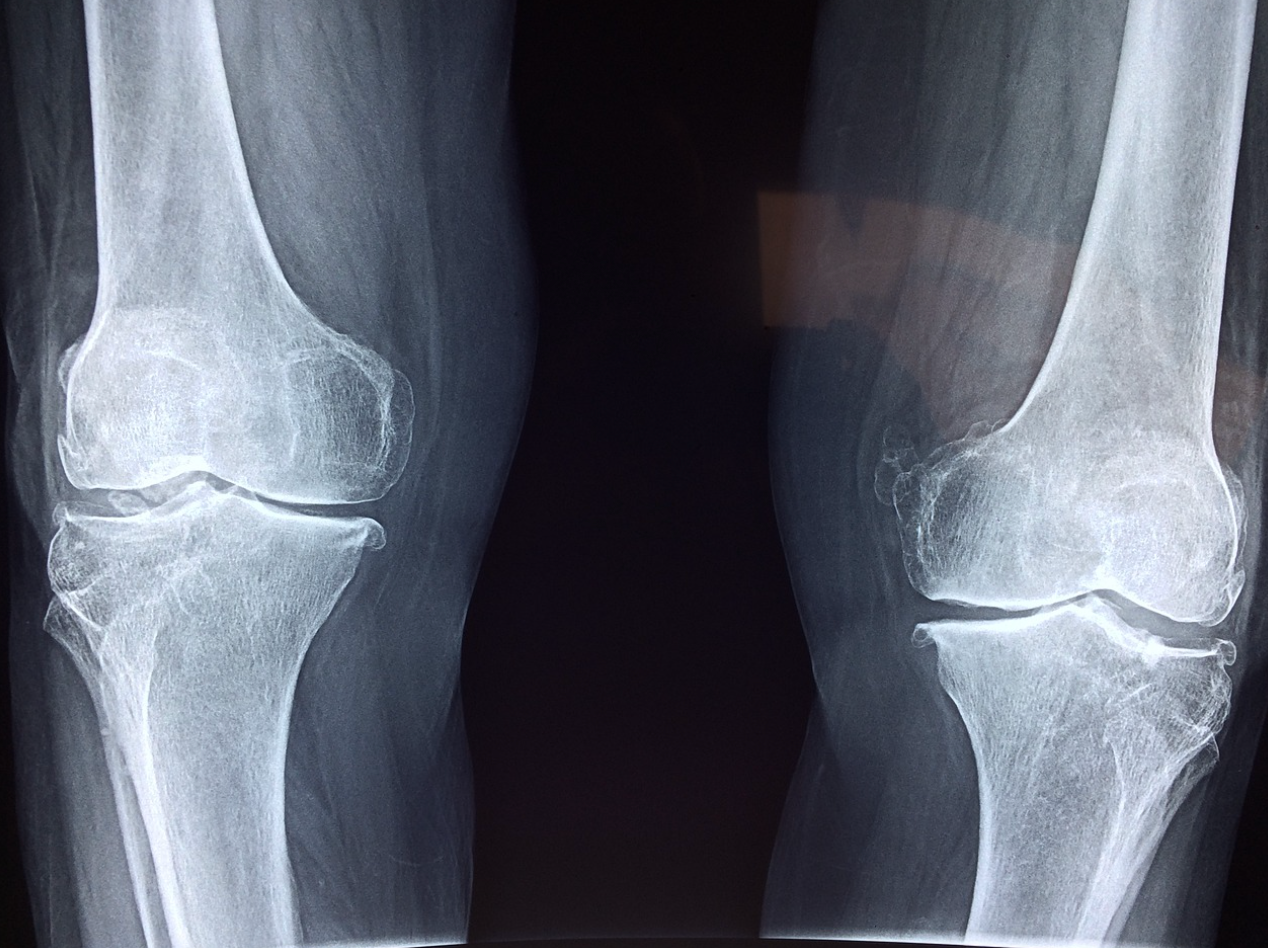

2. 퇴행성 관절염

나이가 들면서 무릎 관절의 연골이 점진적으로 닳아 없어지는 질환인 퇴행성 관절염도 무릎에 물이 차는 주요 원인입니다. 염증 반응이 생기면서 관절 내 액체가 과다 분비됩니다.